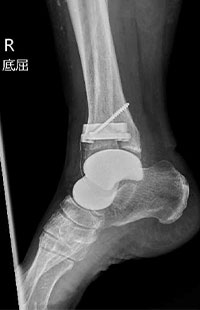

術前

術後